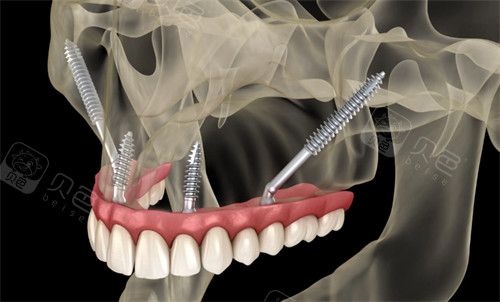

穿颧穿翼种植牙并非普通的牙科手术,它是针对上颌骨极度萎缩、无法通过常规植骨手术修复的患者而研发的高端技术。穿颧种植是将特长的种植体植入到面部的颧骨中,而穿翼种植则是将植体固定在上颌骨后方的翼突处。

这两个部位的骨质密度极高且结构稳定,即便牙槽骨已经流失殆尽,也能为种植体提供强大的支撑力。

普通种植牙主要依赖于牙槽骨的宽度和高度,就像是在土壤中栽树,需要肥沃且厚实的土地。而穿颧穿翼种植则避开了脆弱的牙槽骨,直接在面部的支架骨骼上进行锚定。

穿颧穿翼种植示意图

在植体长度上,普通种植体长度通常在八毫米至十四毫米之间,而穿颧种植体由于需要横跨上颌窦到达颧骨,其长度往往达到三十毫米至五十毫米。在手术难度上,普通种植属于基础外科,而穿颧穿翼则属于颌面外科的范畴,对医生的解剖学功底要求极高。